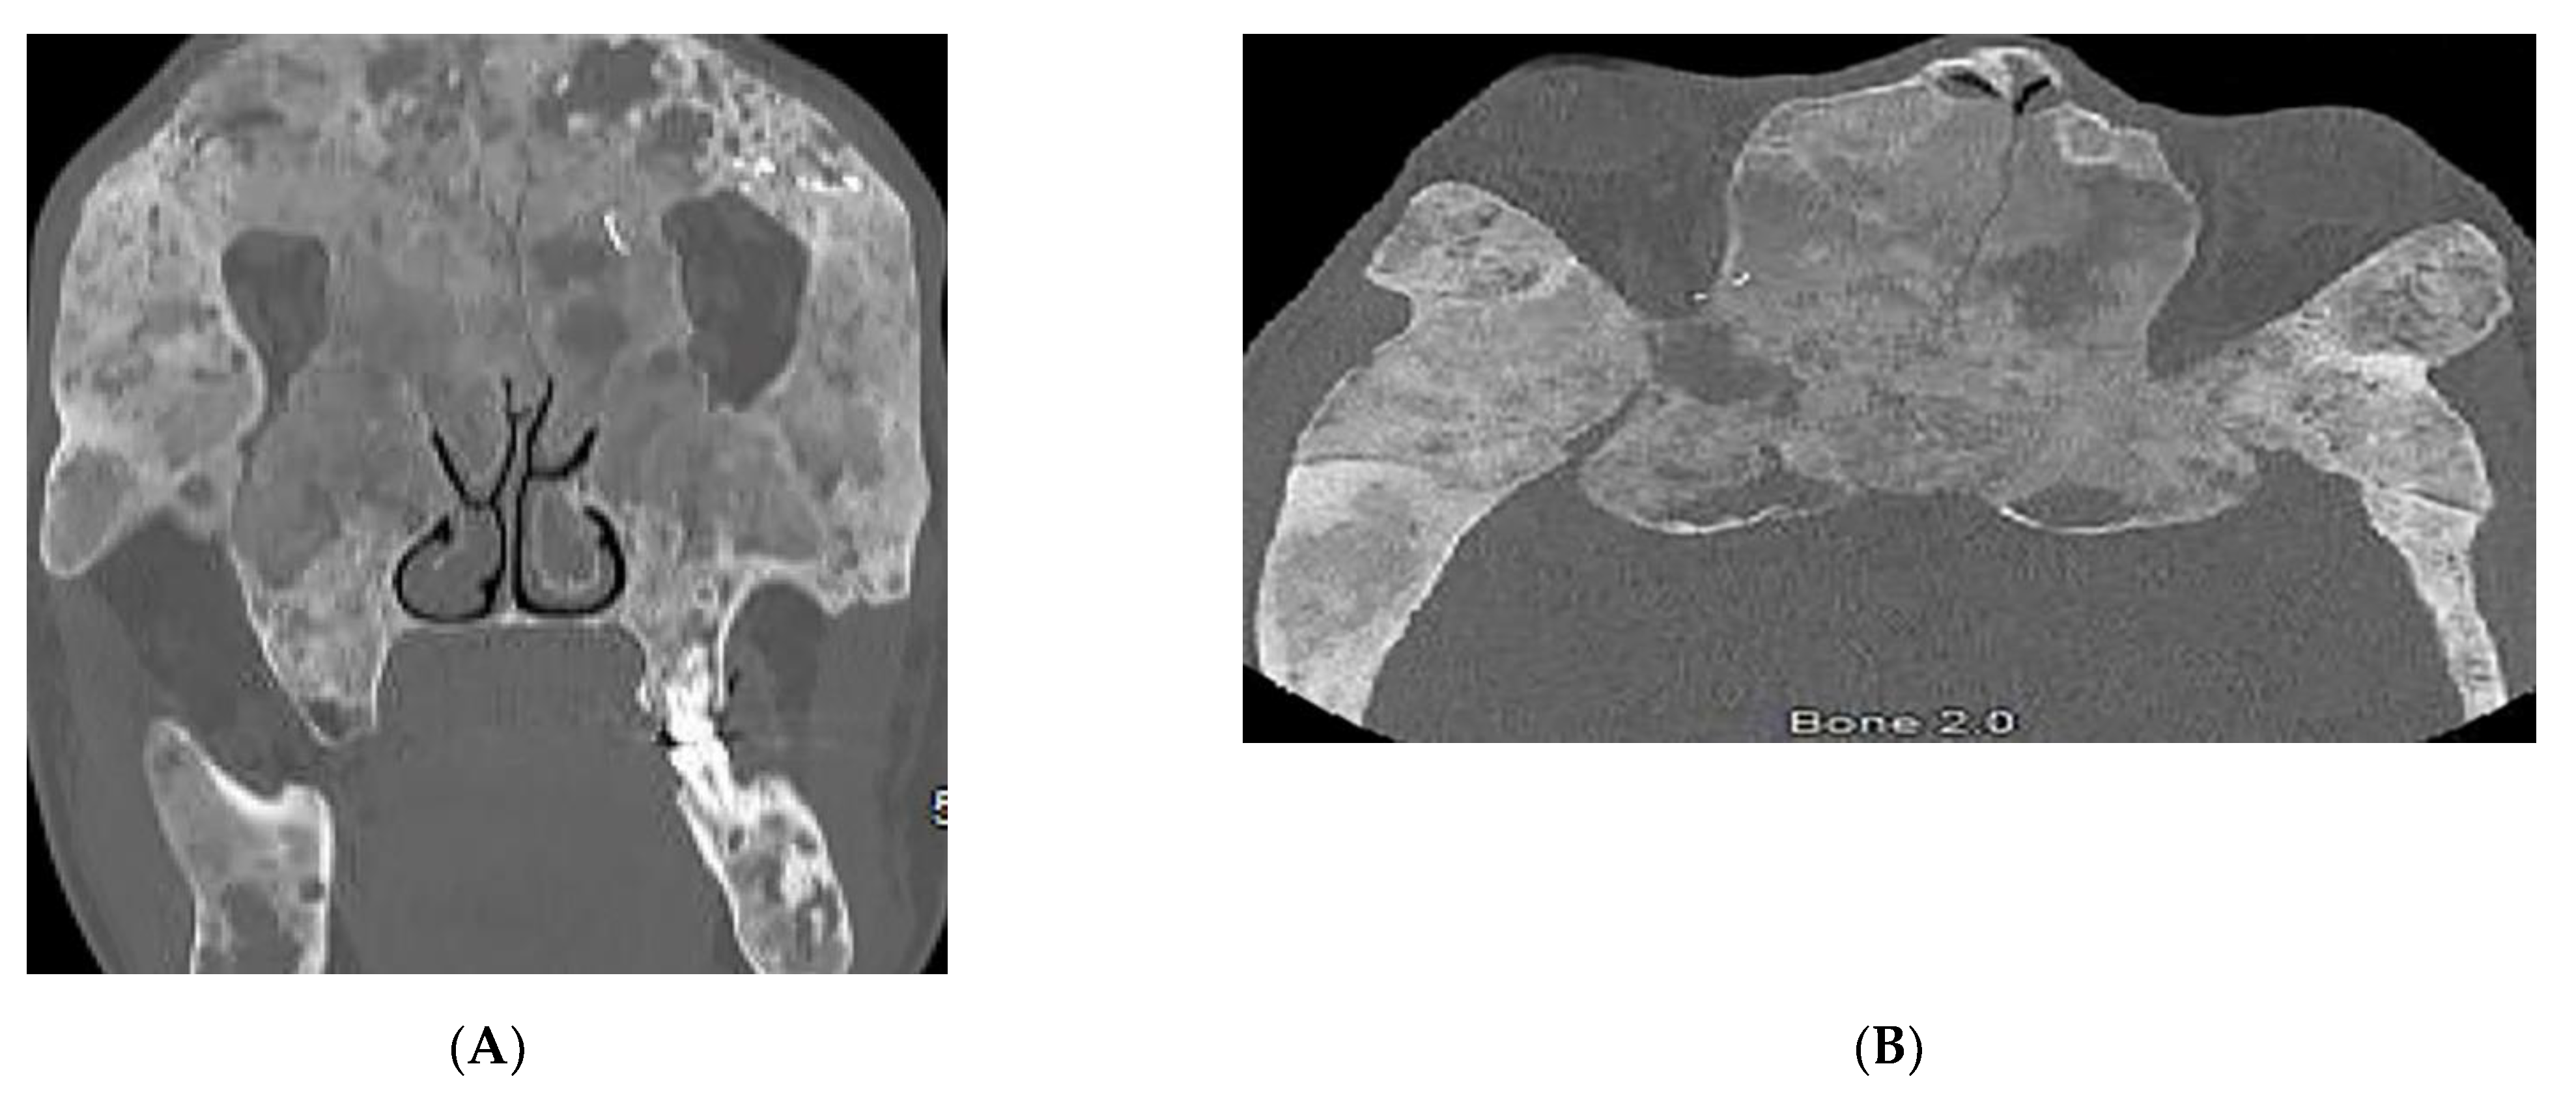

3.5. Nevoid BCC Syndrome (NBCCS)

| Basal cell nevus syndrome | Basal cell carcinomas Palmoplantar pits Skeletal abnormalities Brain abnormalities | Keratocystic odontogenic tumors Ribs and metacarpals abnormalities Medulloblastoma, falx cerebri calcification |